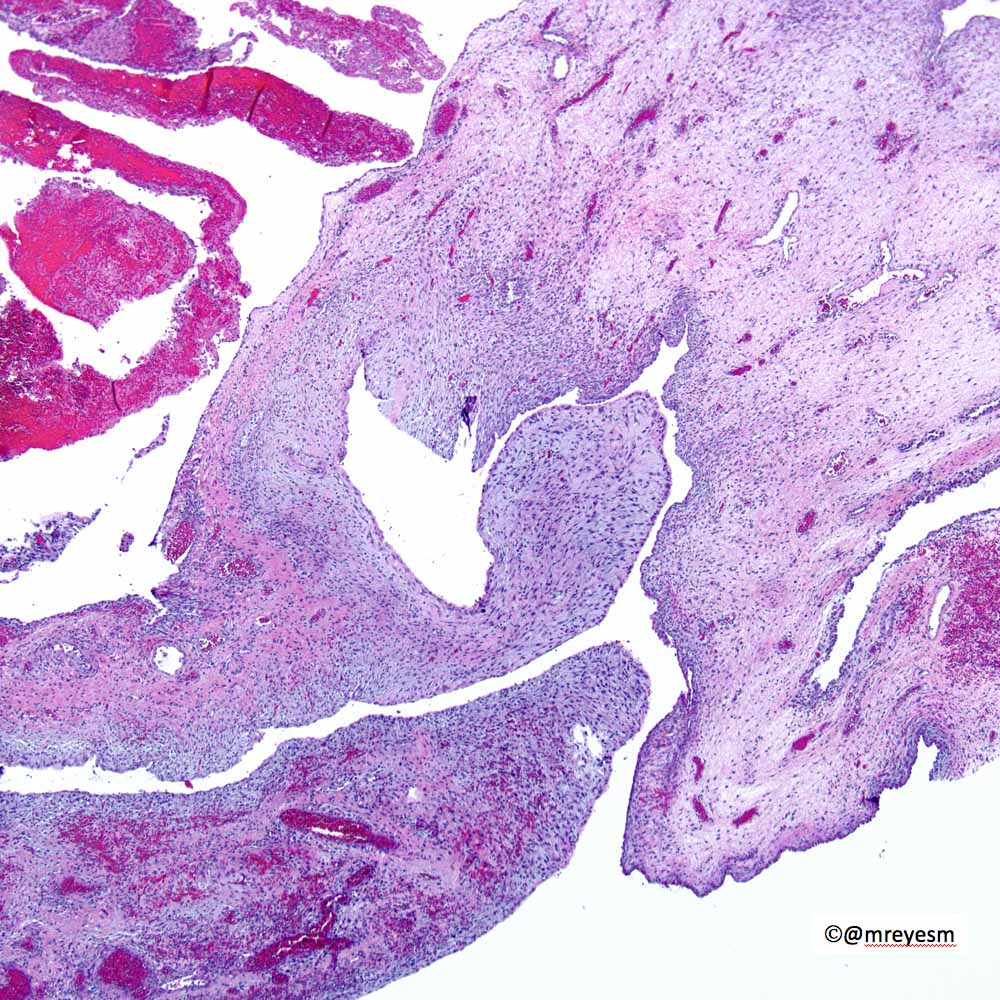

Miguel Reyes-Múgica (@mreyesm) 's Twitter Profile Photo

We have lost a giant of #Pathology and #LungPath #PulmonaryPath.  Dr. Sam Yousem, an admired colleague and friend died yesterday.  He will be missed and remembered.